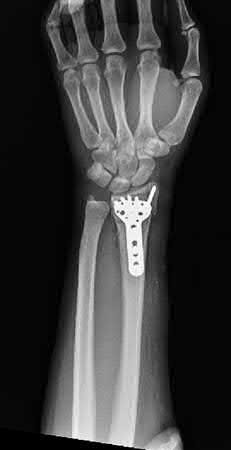

A 51-year-old female presents with an acute inability to extend her thumb, four months after she was treated with cast immobilization for a minimally-displaced distal radius fracture. What is the most appropriate treatment at this time?

A rare complication of non-displaced or minimally displaced fractures of the distal radius treated with a cast is a delayed rupture of the extensor pollicis longus (EPL) tendon. The EPL is the primary extensor of the interphalangeal joint of the thumb and also assists with metacarpophalangeal extension.

Extensor indicis proprius transfer to the EPL is the most widely used and reported treatment for this condition.

Magnussen et al. reviewed results of EIP transfer following ruptures of the EPL, with 19/21 good results. None of the cases had any loss of independent index finger extension although index extensor strength reduced to half of that of the contralateral side.

Hove et al. reported a similar satisfaction rate following treatment of 15 patients. In his series of 4,400 distal radius fractures treated over a 5 year period, the incidence of delayed tendon rupture following distal radius fracture was 0.3 percent.